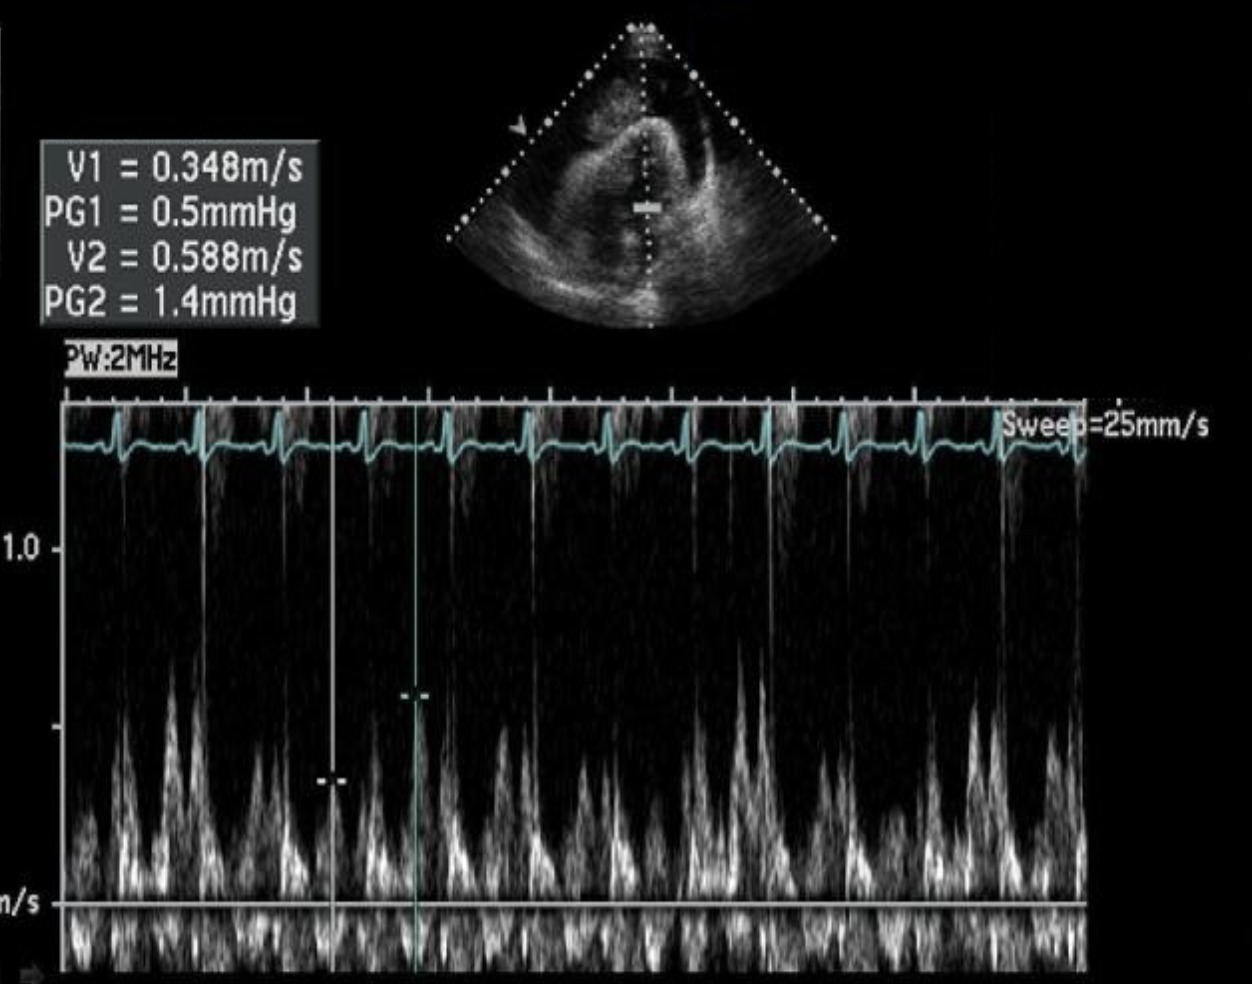

The calipers on the image are measuring?

Abnormal respiratory variation of the E velocities of the mitral valve due to cardiac tamponade

The Doppler tracing is consistent with which of the following cardiac abnormalities?

Constrictive pericarditis